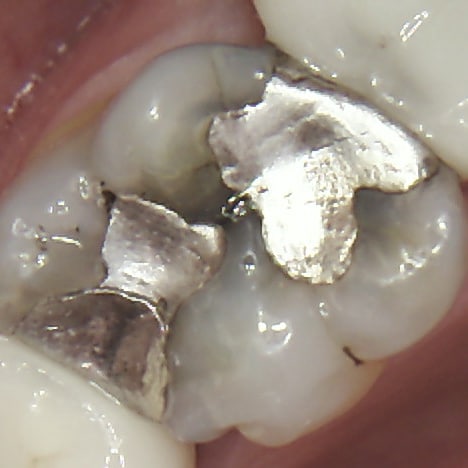

intact amalgam filling

Intact Filling

A perfect filling has a clean, tight seal with the tooth. There are no visible gaps or discolorations along the edges.